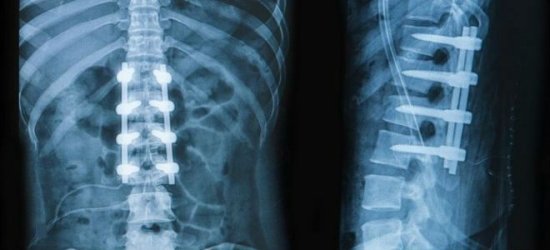

Компьютерная томография является эффективным и высокоинформативным способом выявления различных структурных изменений в позвоночнике, вызванных травматизацией, инфекционным процессом, опухолевыми образованиями, остеопорозом и другими заболеваниями. В основе миелографии лежит применение контрастирующего вещества. Метод применяют при подозрении на стеноз позвоночного канала, грыжевых образованиях, опухолях и других патологических процессах в позвоночнике.